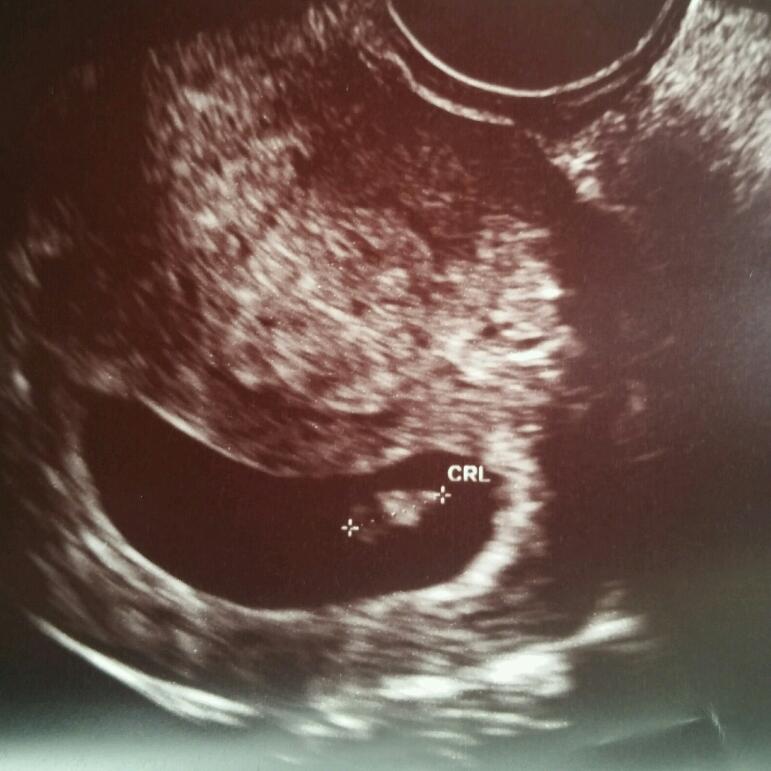

Went in for first official u/s today. 8 weeks 5 days based on LMP. Finally got to see our precious baby and the heartbeat. My OB also pulled out the Doppler and we got to hear it too!! 175 bpm and measuring 9 weeks!! I feel so much better after finally seeing Bean!